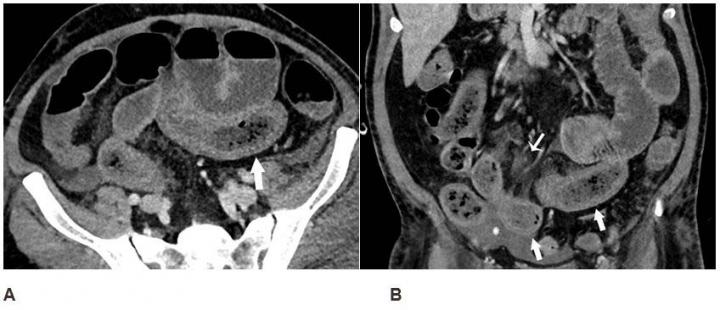

image: Axial (A) and coronal (B) CT of the abdomen and pelvis with IV contrast in a 57-year-old man with a high clinical suspicion for bowel ischemia. There was generalized small bowel distension and segmental thickening (arrows), with adjacent mesenteric congestion (thin arrow in B), and a small volume of ascites (* in B). Findings are nonspecific but suggestive of early ischemia or infection.

Records showed that 17% of patients had cross-sectional abdominal imaging, including 44 ultrasounds, 42 CT scans, and 1 MRI. Bowel abnormalities were seen on 31% of CT scans (3.2% of all patients) and were more frequent in intensive care unit (ICU) patients than other inpatients. Bowel findings included thickening and findings of ischemia such as pneumatosis (gas in the bowel wall) and portal venous gas. Surgical correlation in four patients revealed unusual yellow discoloration of bowel in three of the patients, and bowel infarction (dead bowel) in two patients.